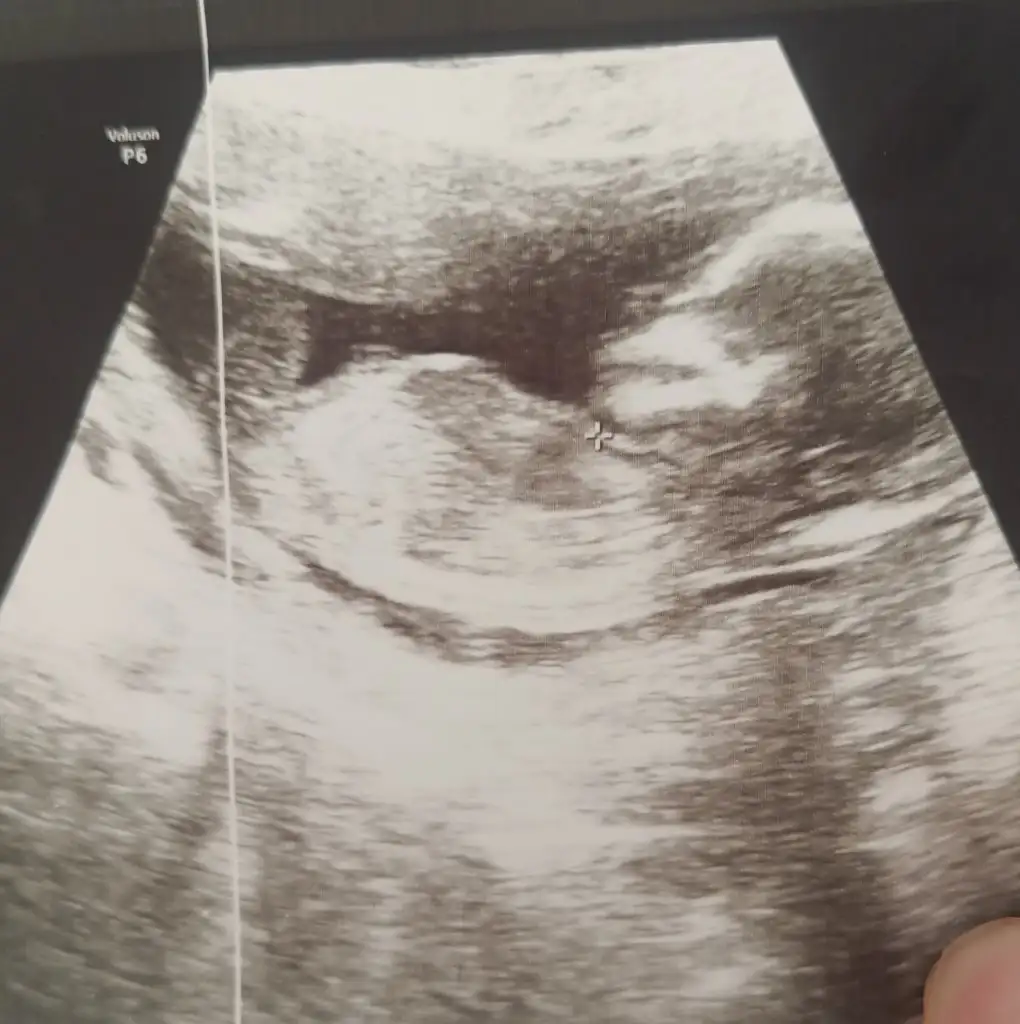

Merhabalar benimkini de yorumlayabilir misiniz acaba 🤗🤗 10+1 haftalık burda. Ama 6-7 gün fazla büyümüş yani 11+1 gibi 🤗🥰